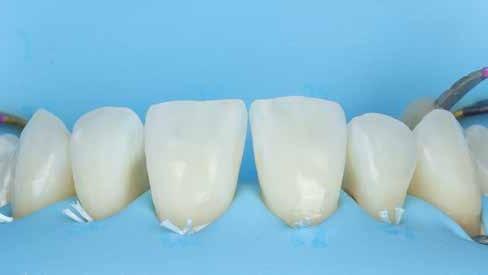

Az alábbi cikkben egy I. osztályú üreg thermo-viszkózus kompozittal, okkluzális matrica technikával történő ellátásának lépéseit ismertetjük (1. ábra). A kofferdám felhelyezését követően az okkluzális felszín anatómiai karakterisztikáját átlátszó, folyékony, fényrekötő kompozit (Clip Flow, VOCO) segítségével rögzítettük. Az anyagot egy bondecset alkalmazásával vittük fel a fog okkluzális felszínére, majd 10 másodpercen keresztül polimerizációs lámpával megvilágítottuk (2–4. ábra). A megkötött átlátszó okkluzális matrica ellenőrzését követően (5. ábra) alkoholba helyeztük (ethanol vagy izopropil-alkohol), az oxigén inhibíciós réteg eltávolítása érdekében. Ezután a szuvas foganyagot eltávolítottuk (6–7. ábra). A zománcot 30 másodpercig, a dentint pedig 15 másodpercig savaztuk (DeTrey Conditioner 36, Dentsply Sirona), majd a felszínt levegő-vízspray segítségével lemostuk (8 –10. ábra). Mivel a fogbélkamrát már csak egy vékony réteg ép dentin fedte, ezért a pulpa vitalitásának megőrzése érdekében az üreg pulpális falait védőréteggel fedtük (DeTrey Conditioner 36, Dentsply Sirona) (11. ábra). Az adhéziót Futurabond DC (VOCO) felhasználásával biztosítottuk. A bondot bondecsettel 20 másodpercen keresztül az üreg falaiba masszíroztuk, majd 5 másodpercen keresztül olajmentes levegő spray-vel megfújtuk a felesleg eltávolítása és a bondréteg elvékonyítása érdekében. A bondot ezt követően 10 másodpercen keresztül polimerizációs lámpával megvilágítottuk (12–13. ábra). Az üreg alját nagyon vékonyan folyékony kompozitréteggel fedtük (GrandioSO Light Flow, A3.5, VOCO), amelyet 20 másodpercen keresztül polimerizációs lámpával megvilágítottuk (14–15. ábra). A bulk-fill tömőanyagot (VisCalor bulk, A2) egy olyan kézi applikátor

2. ábra: A kofferdám felhelyezése. – 3. ábra: A Clip Flow felvitele bondecset segítségével. – 4. ábra: A Clip Flow megvilágítása.